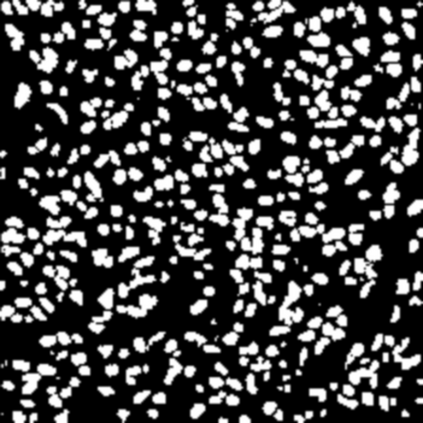

Most recent semantic segmentation methods adopt a U-Net framework with an encoder-decoder architecture. It is still challenging for U-Net with a simple skip connection scheme to model the global multi-scale context: 1) Not each skip connection setting is effective due to the issue of incompatible feature sets of encoder and decoder stage, even some skip connection negatively influence the segmentation performance; 2) The original U-Net is worse than the one without any skip connection on some datasets. Based on our findings, we propose a new segmentation framework, named UCTransNet (with a proposed CTrans module in U-Net), from the channel perspective with attention mechanism. Specifically, the CTrans module is an alternate of the U-Net skip connections, which consists of a sub-module to conduct the multi-scale Channel Cross fusion with Transformer (named CCT) and a sub-module Channel-wise Cross-Attention (named CCA) to guide the fused multi-scale channel-wise information to effectively connect to the decoder features for eliminating the ambiguity. Hence, the proposed connection consisting of the CCT and CCA is able to replace the original skip connection to solve the semantic gaps for an accurate automatic medical image segmentation. The experimental results suggest that our UCTransNet produces more precise segmentation performance and achieves consistent improvements over the state-of-the-art for semantic segmentation across different datasets and conventional architectures involving transformer or U-shaped framework. Code: https://github.com/McGregorWwww/UCTransNet.